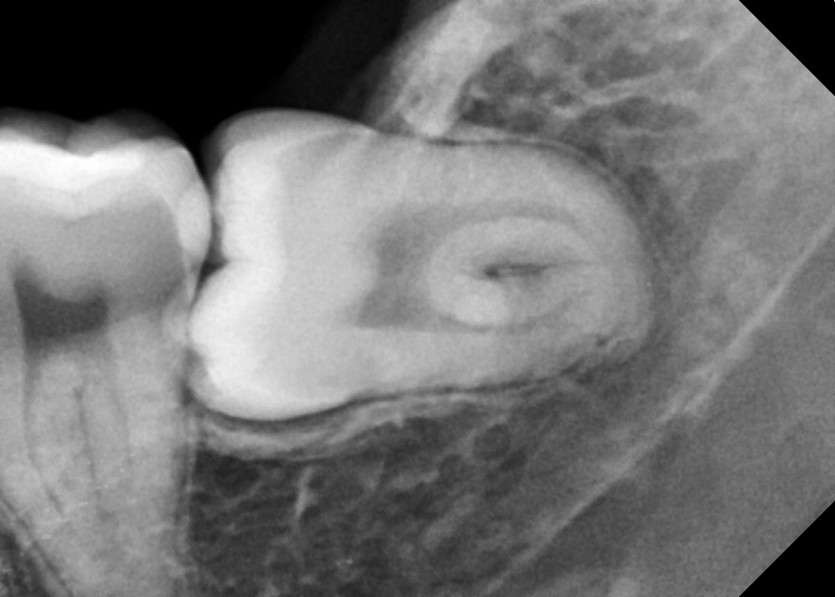

#28,38 사랑니 발치

구강 외과 전문의가 당일 발치했습니다.